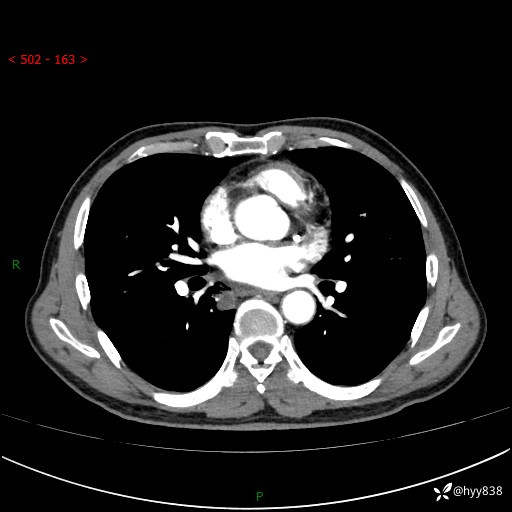

胸部CT平扫+增强